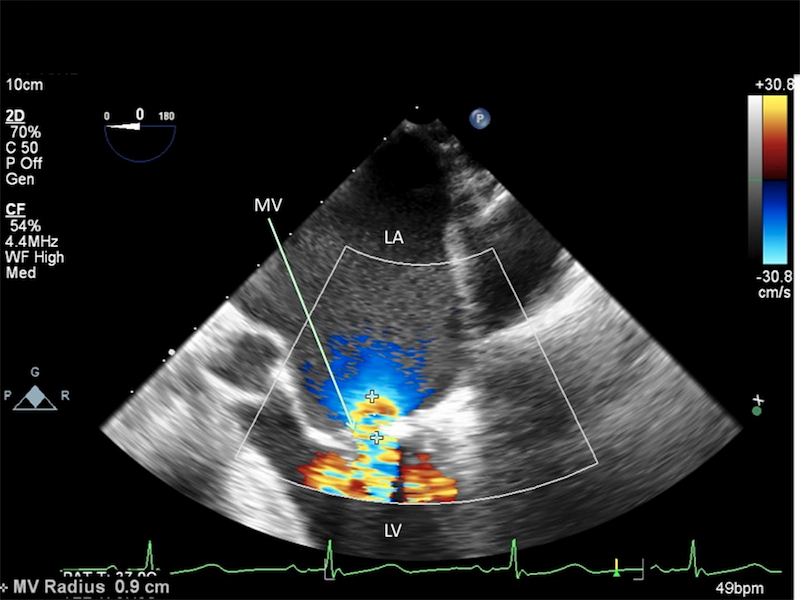

Make the diagnosis and describe the findings.

Mitral stenosis

Transesophageal echocardiogram 2-dimensional midesophageal view of mitral stenosis. Mitral valve (MV) with minimal opening during diastole. Flow acceleration of color Doppler indicates significant left atrium (LA) to left ventricular (LV) gradient. This patient requires a prolonged diastolic phase for adequate LV filling and ultimately cardiac output.

How does mitral stenosis affect PAOP?

PAOP will be overestimated.